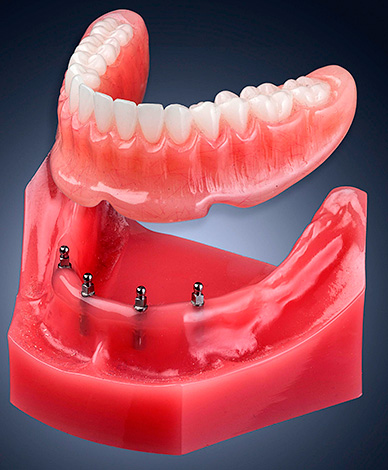

Como observado acima, os mini-implantes costumam ser usados para fixar próteses removíveis. Dependendo do tamanho da prótese, um número diferente de implantes pode ser instalado na mandíbula, na qual uma única prótese é então acoplada. Isso proporciona uma fixação rígida da prótese, sua imobilidade ao comer e conversar e, mais importante, o conforto geral do uso. Ao mesmo tempo, a prótese em si pode ser removida e instalada nos implantes várias vezes e, ao usar alguns tipos de pilares, um número ilimitado de vezes.

Ao mesmo tempo, a prótese em si é fixada com muita segurança em implantes - essa é outra vantagem importante dessa versão das próteses. Devido à fixação rígida, torna-se possível reduzir o tamanho da base plástica da prótese, tornando-a menos volumosa e quase invisível para o paciente (não haverá reflexo de vômito, alterações de dicção e diminuição das sensações gustativas).

- Esférico tradicional - menos durável e exigindo substituições mais frequentes. Na prótese para tais pilares, são feitos ninhos esféricos nos quais existem travas de metal com vedação de silicone. Quando a prótese é colocada em implantes, o pilar esférico entra na matriz de silicone e é fixado nela. Plantada em vários implantes, a prótese é rigidamente fixada a eles;

Fixação da prótese: métodos possíveis

As próteses removíveis podem ser fixadas em mini-implantes de duas maneiras: usando matrizes de silicone (acessórios) e sem elas. No primeiro caso, a carga durante a mastigação será de alguma forma distribuída entre os implantes (e, portanto, o osso em que estão fixados) e os tecidos moles. No segundo caso, o implante não será carregado e toda a pressão será distribuída apenas ao longo da gengiva, mas ao mesmo tempo as próteses serão fixadas com segurança suficiente para evitar a mobilidade durante a mastigação ou a fala.